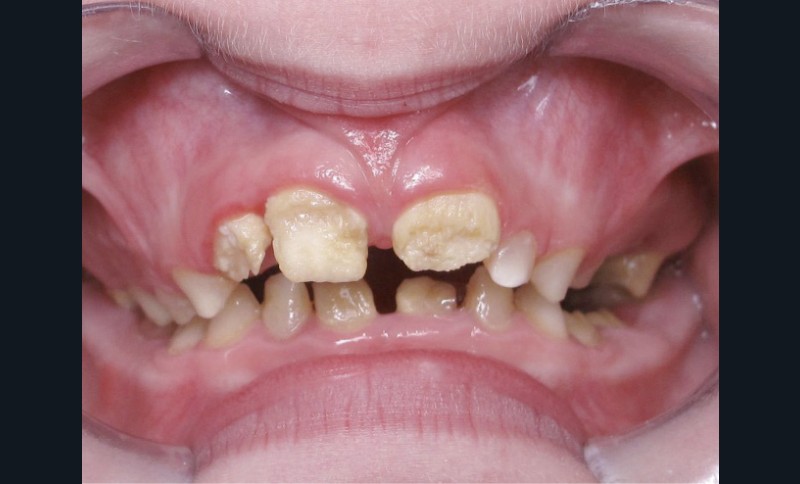

Il existe des anomalies dentaires (tabl. I) [1-12], mais aussi occlusales associées aux AI (fig. 1 et 2).

Selon de nombreuses études, l’anomalie occlusale la plus fréquemment retrouvée en association avec les AI est l’infraclusion antérieure, puisqu’elle est retrouvée chez 22 à 64 % des patients présentant cette affection, et encore plus chez les femmes [2,8,13-19]. Cette anomalie touche tous les types d’AI mais à des degrés très divers. Son incidence semble élevée dans les formes hypominéralisées, moindre dans les formes hypoplasiques et nettement moindre dans les formes hypomatures [8,17,18]. La sévérité de l’atteinte amélaire ne semble pas corrélée avec la présence ou l’intensité de cette malocclusion [17].